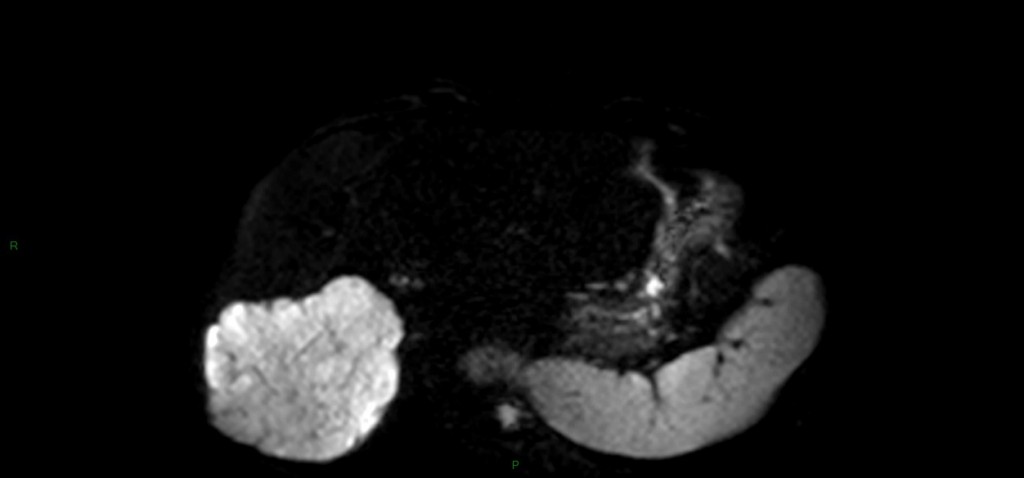

Tumeurs hépatiques – Angiome hépatique Alexandre Ladoux il y a 11 ans ANGIOME CAVERNEUX A reconnaître +++ Unique 90% 80% < 4cm Franc hT1, HT2 liquidien, contours polylobés, disparait en bili-IRM Prise de contraste en mottes discontinues, précoce, avec remplissage centripète (lacs veineux) progressif jusque complet (tardif+++) Possible portion liquidienne centrale : dégenerescence mucoïde ANGIOME CAPILLAIRE (hémangiome) Pdc intense équivalent à l’aorte à tous les temps Diagnostic en échographie : si 4 critères présents Hyperechogène homogène, sans signal Doppler couleur +- renforcement postérieur < 3cm Bilan hépatique normal En dehors de contexte néoplasique DDx : lésions fibreuses avec remplissage centripète: Cholangiocarcinome fibro-lamellaire : Pdc périph mais CONTINUE Métastase d’ADK colique mucineux (HT2 liquidien) ou neuroendocrine : Pdc tardive périph CONTINUE jamais complète Exemples d’angiomes hépatiques Angiome géant Angiomes et adénome graisseux Partager : Partager sur Facebook(ouvre dans une nouvelle fenêtre) Facebook Partager sur LinkedIn(ouvre dans une nouvelle fenêtre) LinkedIn Partager sur X(ouvre dans une nouvelle fenêtre) X Partager sur WhatsApp(ouvre dans une nouvelle fenêtre) WhatsApp Envoyer un lien par e-mail à un ami(ouvre dans une nouvelle fenêtre) E-mail Imprimer(ouvre dans une nouvelle fenêtre) Imprimer Plus Partager sur Tumblr(ouvre dans une nouvelle fenêtre) Tumblr Partager sur Pinterest(ouvre dans une nouvelle fenêtre) Pinterest